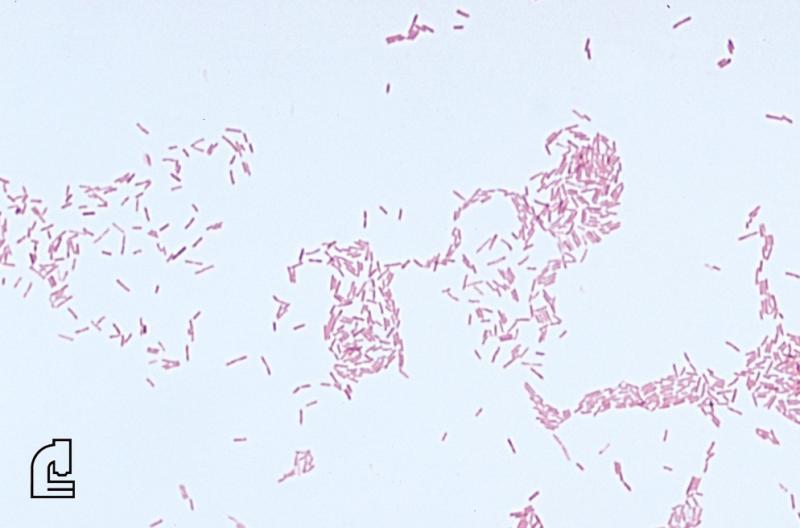

- Gram Stain